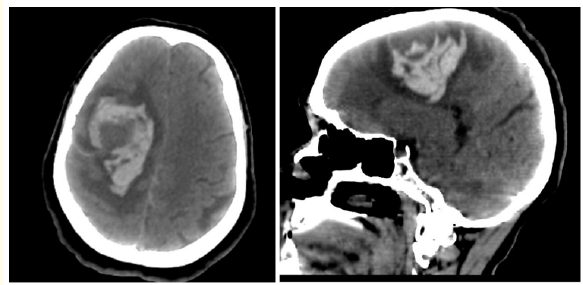

Intracerebral Hematoma Revealing a Meningioma: About a Case and Review of the Literature

N Amsiguine, K Imrani, N Moatassim Billah and I Nassar. 15(7): 24-28.